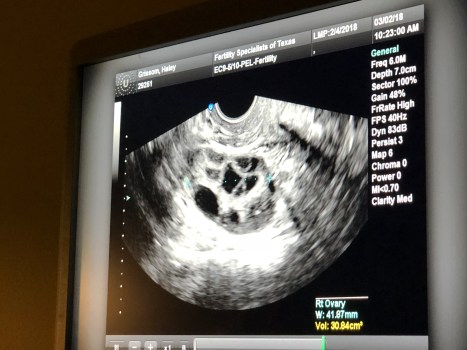

Why Not Me, Why Not Us?